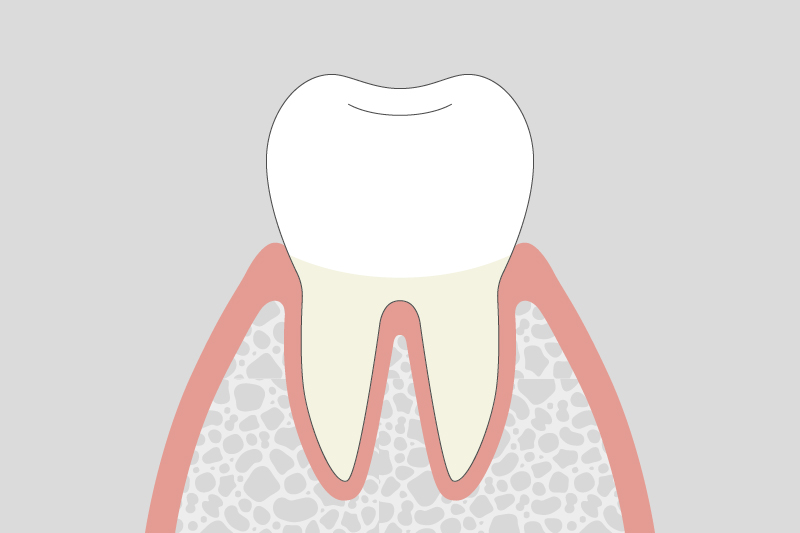

歯肉炎(軽度)

歯ぐきが赤く腫れ、出血しやすくなる。